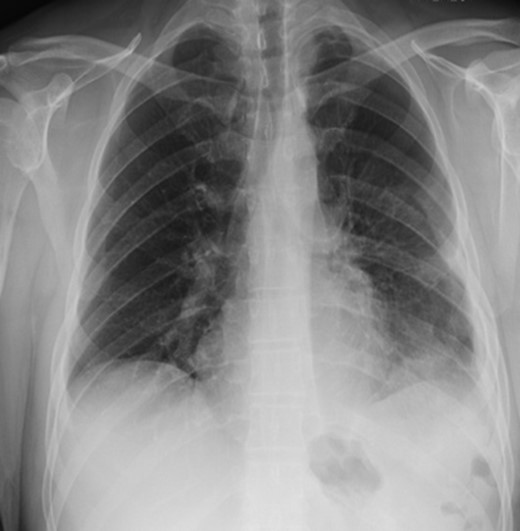

Two days later, the patient re-presented to the emergency department with left-sided pleuritic chest pain. The heart rate was 92 beats/min and the respiratory rate was 23 breaths/min on room air. The patient was stable, looked well, and his pain resolved almost entirely at time of examination. Clinically relevant labs showed a WBC of 8 × 109/L (normal range: 4–11 × 109/L). The CT did not show any significant enlargement of pneumoperitoneum; however, significant rightward shift of the mediastinum was noted. So we suggested worsening tension in the left hemithorax with further collapse of the left lung (Fig. 3). Despite being clinically stable, the mediastinal shift which was not present on the previous admission was concerning and thus the patient was taken to the operating room with the decision to repair the hernia. A left thoracotomy was used to enter the chest cavity. There was severe atelectasis of upper and lower lobes. We immediately noted a large hernia sac which encompassed the entire chest cavity and the remaining diaphragmatic muscle was significantly thinned out. The hernia sac was opened in order to identify the source of the pneumoperitoneum seen on imaging which we had suspected to be of gastric origin. Upon examination of the abdominal contents which required meticulous dissection off the herniated diaphragm from chronic adhesions, we were able to identify a well-developed perforated gastric ulcer on the anterior surface of the greater curvature of the stomach (Fig. 4). This ulcer was resected with a wedge GIA stapler and the hernia was subsequently closed by bringing the muscles together and imbricating the closure with the redundant sac using prolene sutures. Upon closure, we did not place a mesh due to the possible contamination from the gastric perforation. When the repair was complete and the patient taken off the one-lung ventilation, his lungs immediately pinked up and re-expanded. Overall, the patient tolerated the procedure very well without any post-operative complication. Two days later, we carried out an upper GI series which showed no evidence of any extravasation and his diet was advanced. On the sixth post-operative day, the patient was discharged home. He was re-evaluated in clinic 2 weeks later and continued to progress well with a stable repeat chest x-ray (Fig. 5).